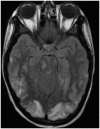

Results: Eight out of the 20 patients included in the study were on cyclosporine or tacrolimus based immunosuppressant therapy for kidney transplant. Four patients had severe hypertension at presentation. The most common MRI finding was high T2-fluid-attenuated inversion recovery (FLAIR) signal in the cortex and subcortical white matter of both cerebral hemispheres, particularly in the parietal and occipital lobes (n=16). The second most common MRI finding was increased leptomeningeal FLAIR signal (n=7). Out of seven patients with leptomeningeal signal, five demonstrated leptomeningeal enhancement as well. Four out of these seven patients had no other parenchymal findings.